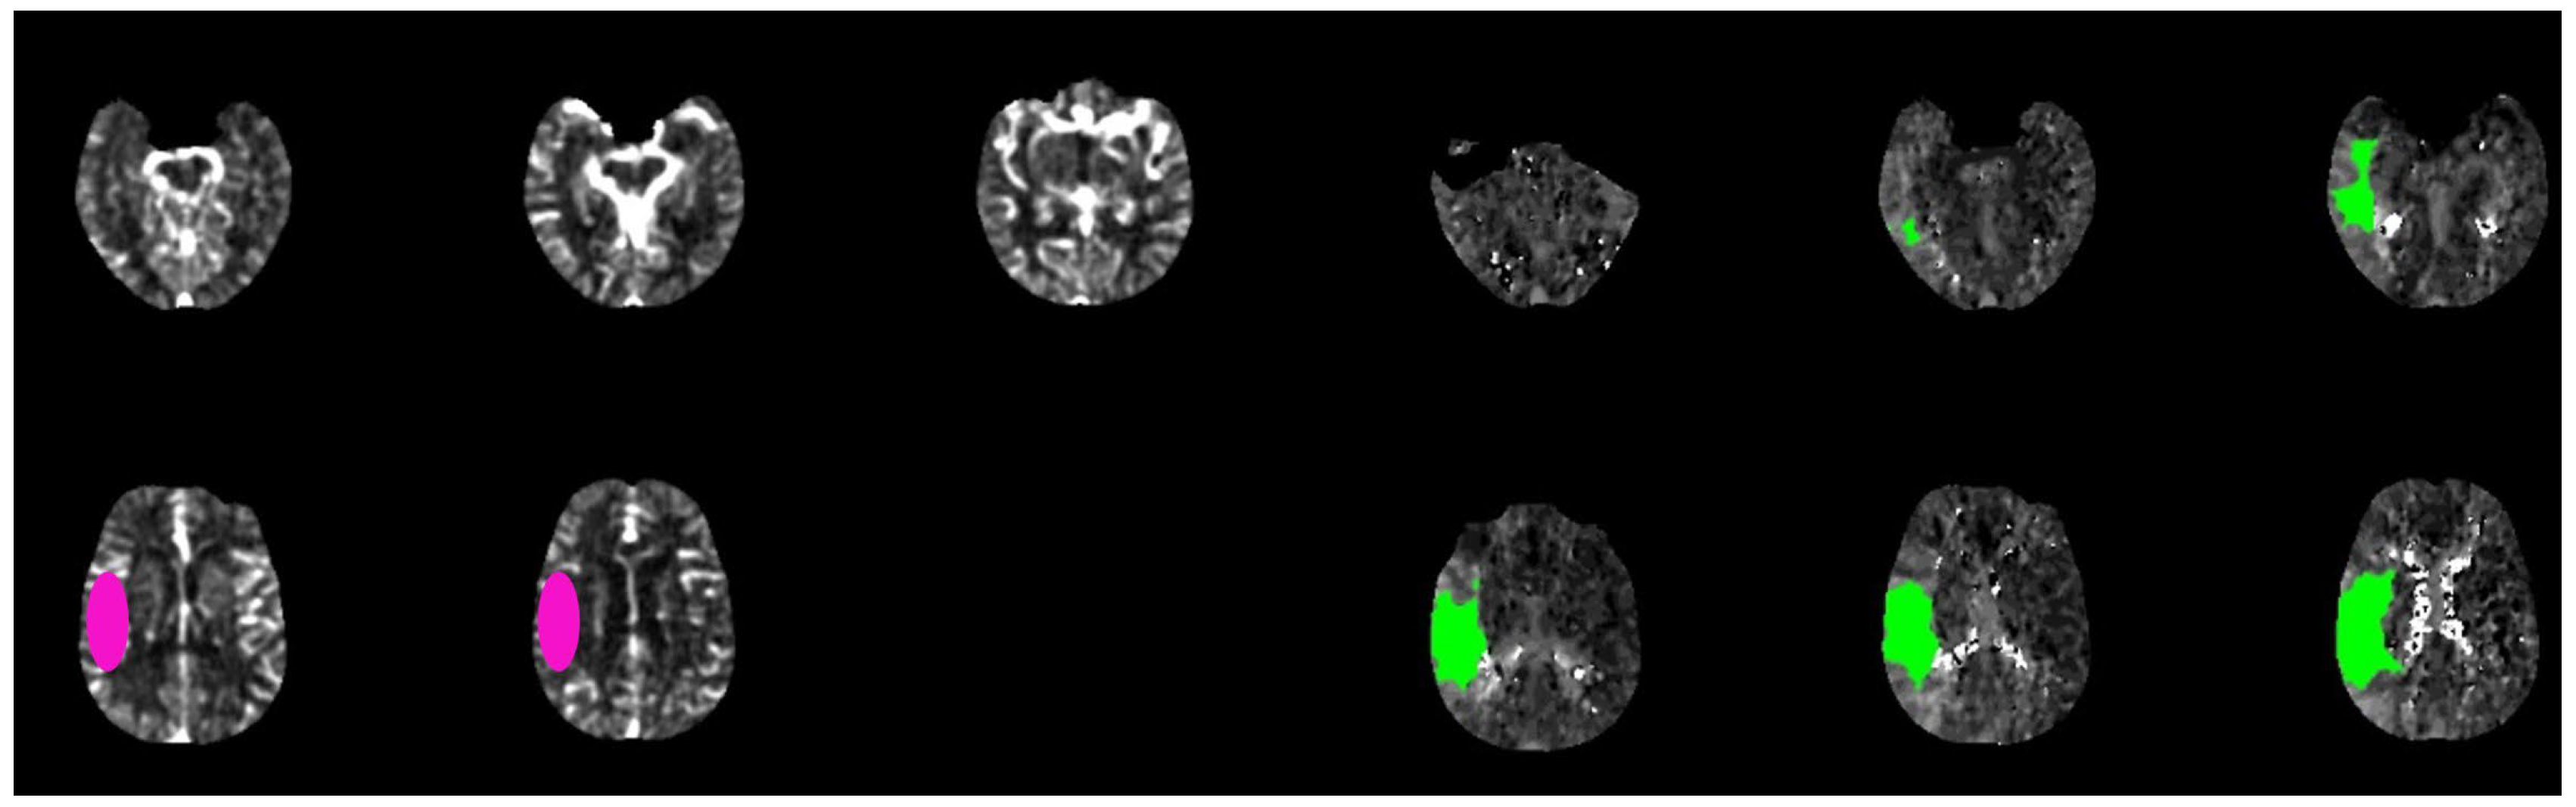

3. Imaging

3.2. Automatic Assessment